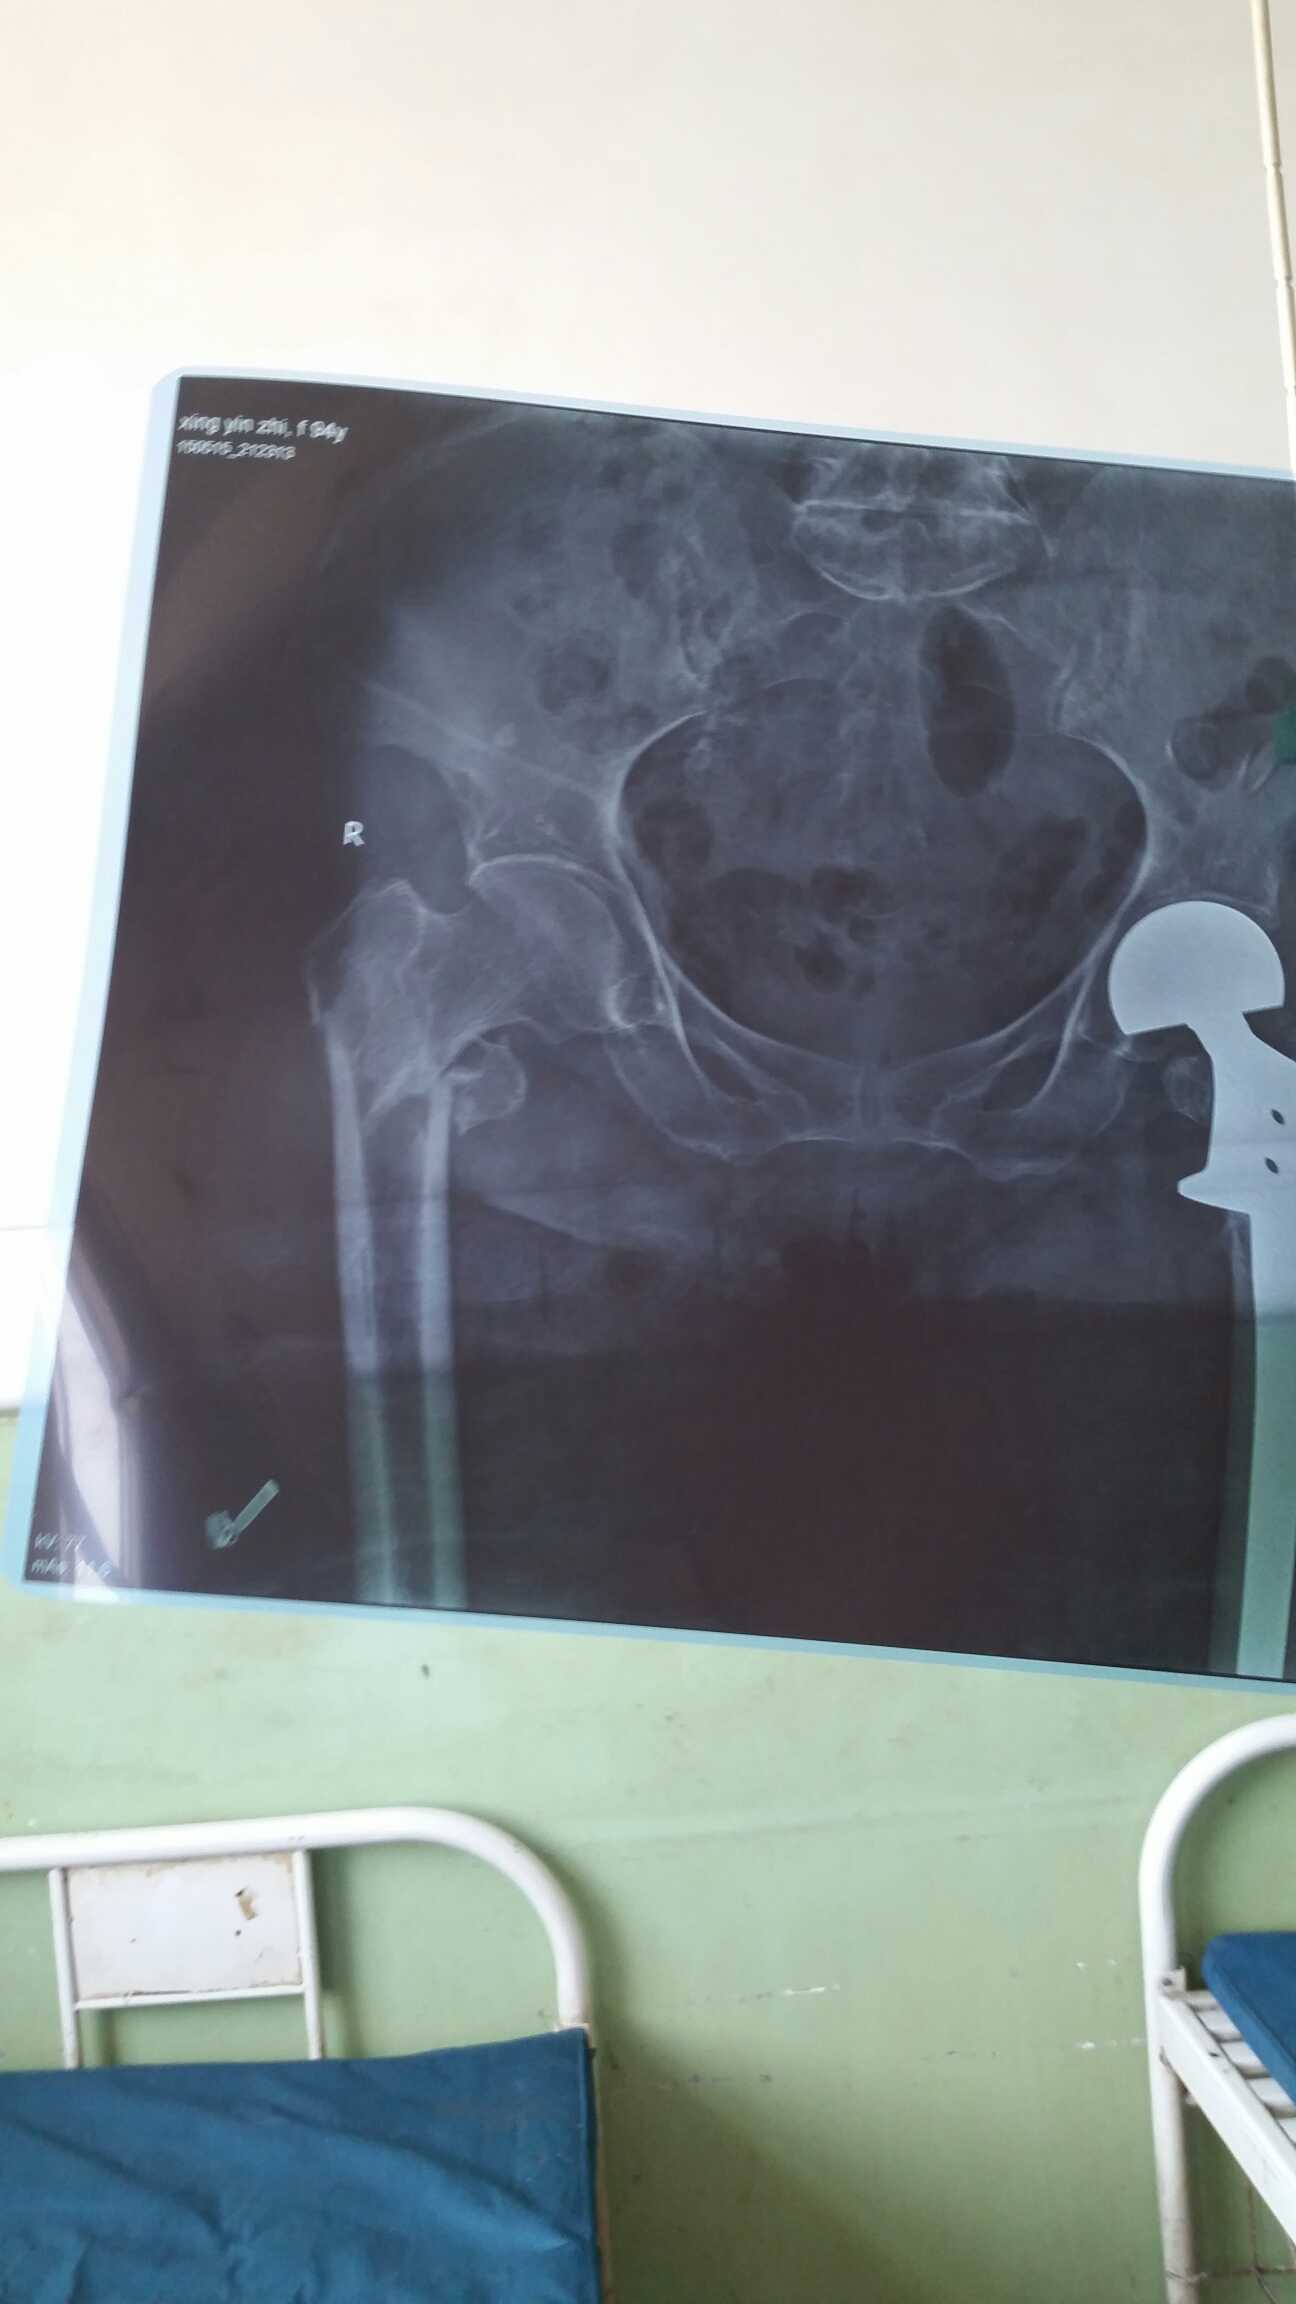

女,95,摔伤后右髋部疼痛伴右下肢活动受限半小时入院。八年前有左股骨头置换术。平素高血压十年,口服尼莫地平、阿司匹林治疗,血压控制理想,生活自理